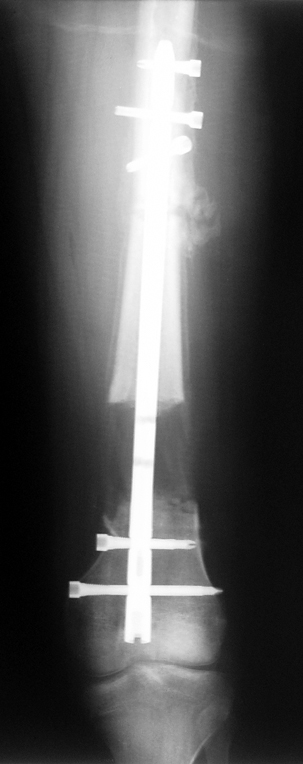

3. POSTTRAUMATIC LOWER LIMB SHORTNESS (MALUNION)

This type of shortness occurs after a fracture heals in a shortened position. Most cases are seen in adults and can be treated with one lengthening operation. Additional deformities can be corrected simultaneously. Most of these cases can be treated with lengthening over nail or just corrections and intramedullary nailing.